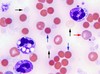

Red Cell Ghosts (black arrows)

Red Cell Ghosts - RBCs w/o Hb indicate intravascular lysis

Associations

-fulminant bacterial infections eg clostridium perfringens

Normocyte/Nucleated RBC

Not normal in peripheral blood

Association - severe haemolysis, hypoxaemia, myelofibrosis